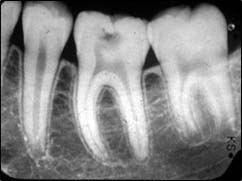

Il s'agit de radios de petites tailles placées et orientées dans votre bouche et ciblant un secteur de une à trois dents. Elles permettent une vision plus précise de certains détails.